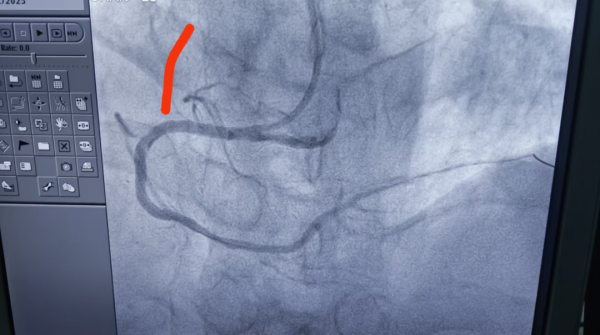

1、39岁男性,前降支闭塞,行血栓抽吸+冠脉内溶栓。

2、71岁男性,右冠闭塞,行药物球囊扩张成形术。

3、69岁男性,双支病变,行介入治疗。